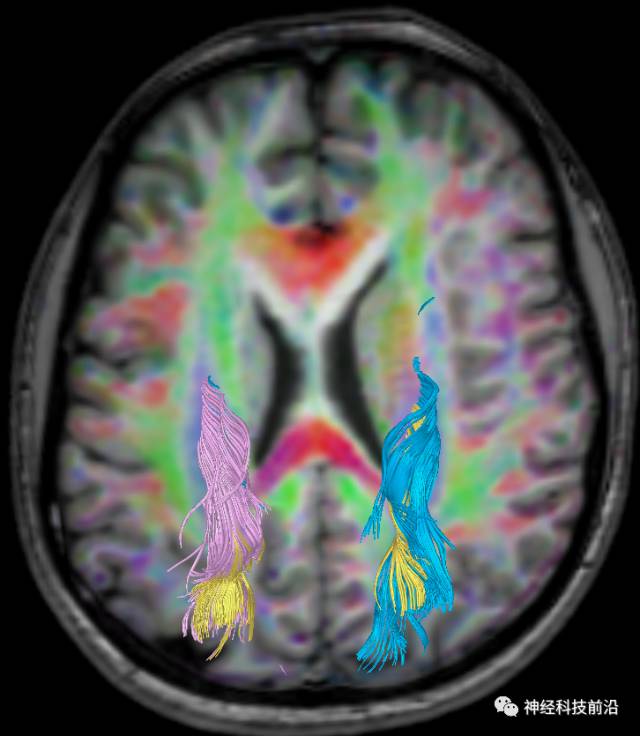

皮质脊髓束与皮质脑桥束的关系毗邻

脑干内高信号为一近环形纤维束,其作用尚待研究。

上述纤维束与小脑中脚的位置毗邻

终上所述:脑干高信号为一近环形纤维束,内囊后肢高信号为皮质脑桥束,皮质脊髓束在中脑位置略靠后。高信号位于中脑前缘,是皮质脑桥束的位置所在,另外有部分桥连纤维。